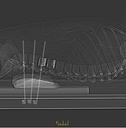

Dieses weltweit einmalige Phantom bietet erstklassige Übungsmöglichkeiten für die Lagerungs- und Einstelltechnik in der Projektions-Radiographie und gehört eigentlich zur Grundausstattung jeder Röntgen-Ausbildungsstätte. Das Phantom enthält ein natürliches menschliches Skelett sowie die Umrisse von Kehlkopf, Lunge, Herz und Nieren (Organe erscheinen als Schatten auf den Röntgenbildern), dadurch können mit dem Phantom echte Röntgenaufnahmen wie beim Patienten gemacht werden. Durch die Verwendung des echten Skeletts können Leitstrukturen im Knochen erkannt werden, was bei Kunststoffskeletten nicht möglich ist. Bei der Montage des Phantoms wird besonderer Wert auf die Darstellung der Gelenkspalte gelegt. Die Gelenke sind voll beweglich montiert, und ermöglichen die Lagerung in den normalen Röntgenpositionen (z.B. Froschposition, Pro- und Supination des Unterarms). Die Arme können nach oben bewegt werden, so dass das Modell auch für alle knöchernen Untersuchungen im CT verwendet werden kann. Bei jedem Phantom handelt es sich um ein handgefertigtes Unikat, welches sich in Größe und Ausführung unterscheiden kann. Je nach Modell können pathologische Befunde vorhanden sein, die äußere Erscheinung kann sich je nach Größe des Modells unterscheiden. Die neue Ausführung dieses Modells wurde in Zusammenarbeit mit einer namhaften deutschen Schule für Med. Techn. Radiologieassistenten komplett überarbeitet und erfüllt alle Anforderungen für die Ausbildung. Der Verkauf dieses Phantoms erfolgt nur gegen Nachweis der medizinischen Verwendung. Natürliche Größe.